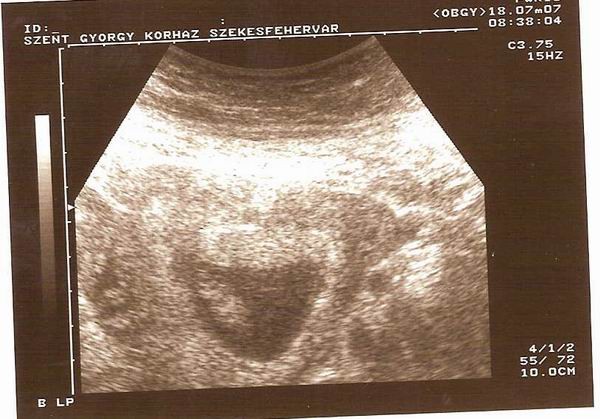

Reggeli uh eredmény 19 mm kis maszatka, és február 23 a szülés ideje. Ani, majd a táblit módosítsd légyzi. A vonalzómat is módosítani fogom később.

Kaptam képet is, amit nem tudok feltenni, mert baromi nagy, majd délután próbálkozok. Akkor jobban lesz időm.

Íme kis maszatka sztárfotója.